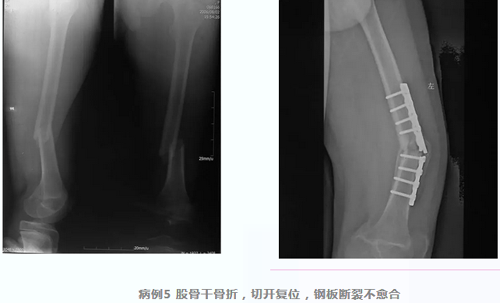

弹性髓内针

儿童长骨骨折传统的治疗方式也是保守治疗,而确实需要手术的患者如果选择切开复位钢板固定的方式,不可避免地增加了手术创伤,同时感染、骨折不愈合、内固定断裂、内固定取出后再骨折的发生率相对高发,因此,专门为儿童开发的弹性髓内针成为治疗儿童长骨骨折的首选。闭合复位经皮置入髓内针,进针点皮肤切口仅1-2cm,不仅微创而且固定牢靠,愈合后取出容易。